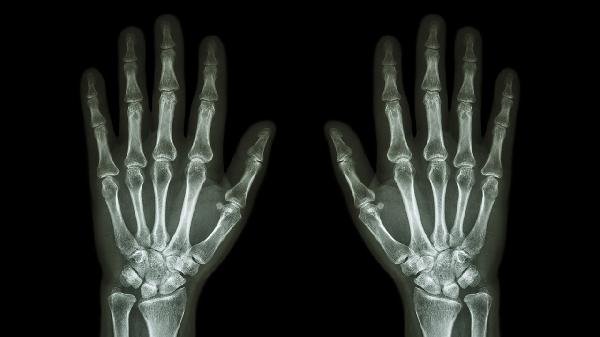

手指关节触摸有刺痛感可能与关节劳损、骨关节炎、类风湿关节炎、痛风性关节炎或腕管综合征等因素有关。刺痛感通常由局部炎症、神经压迫或代谢异常引起,建议及时就医明确病因。

关节软骨退变会引发骨赘形成,刺激周围组织产生刺痛。中老年人群多见,伴随晨僵和活动受限。医生可能建议服用硫酸氨基葡萄糖胶囊,配合关节腔注射玻璃酸钠注射液改善功能。

日常应注意保持手部温暖,避免冷水刺激。进行手指伸展操改善血液循环,控制每日手机电脑使用时间。若刺痛持续超过两周或伴随关节变形、发热等症状,须尽快至风湿免疫科或骨科就诊,完善X线、超声或血液检查。饮食上增加深海鱼类摄入,补充欧米伽3脂肪酸有助于减轻炎症反应。